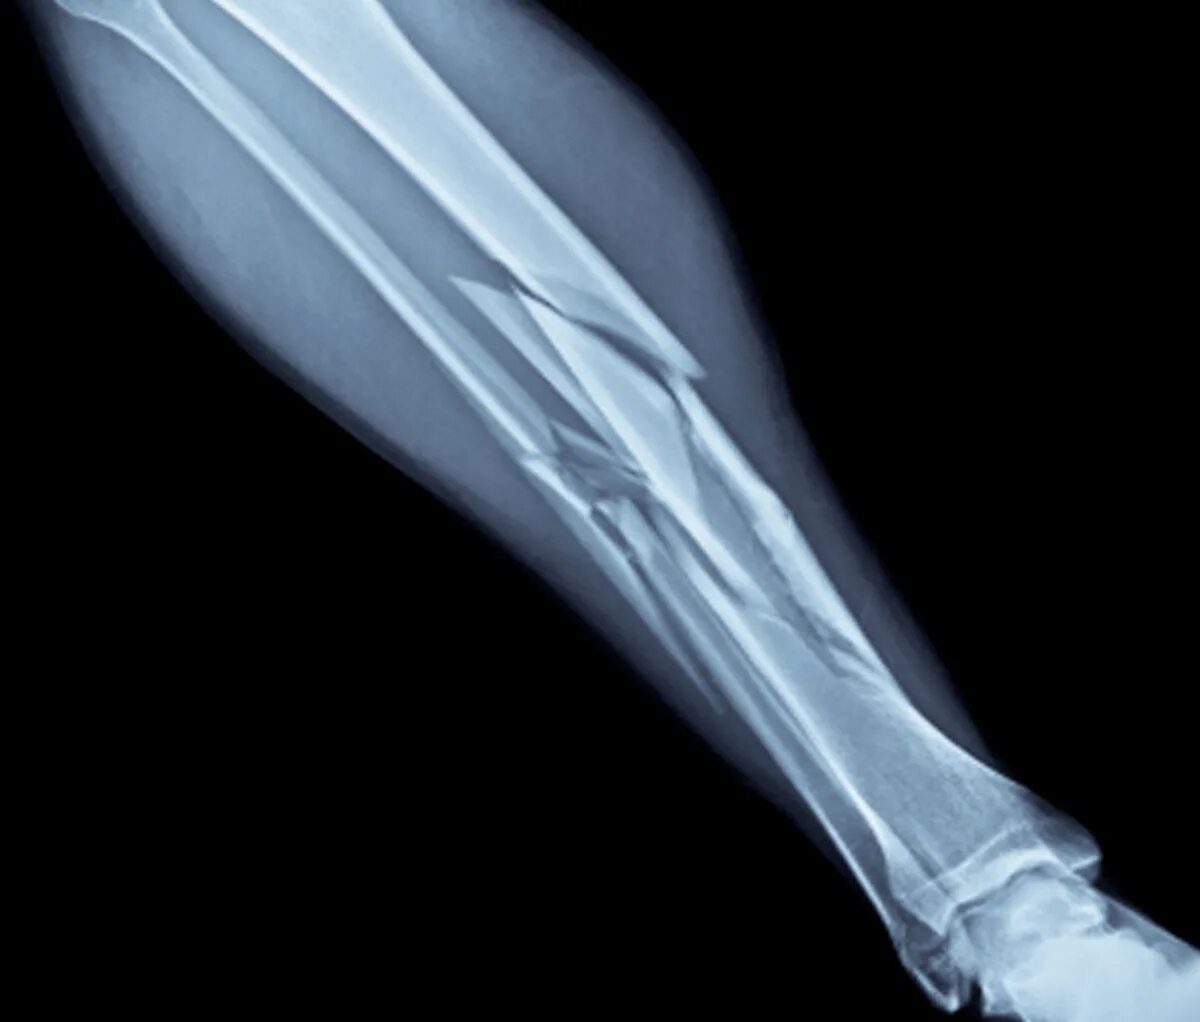

A fracture is a broken bone